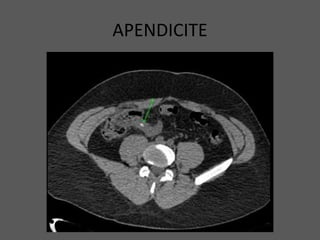

APENDICITE